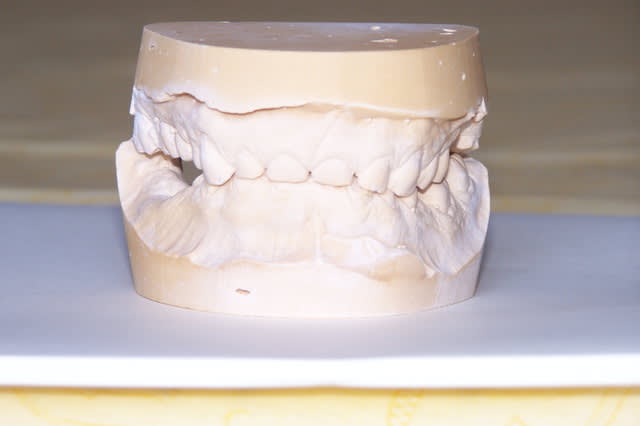

Des modèles d’étude ont été réalisés.

- enregistrement occlusion en relation centrée + wax up de 15 à 27 et de 47 à 37 + réalisation de provisoires en fonction du wax up.